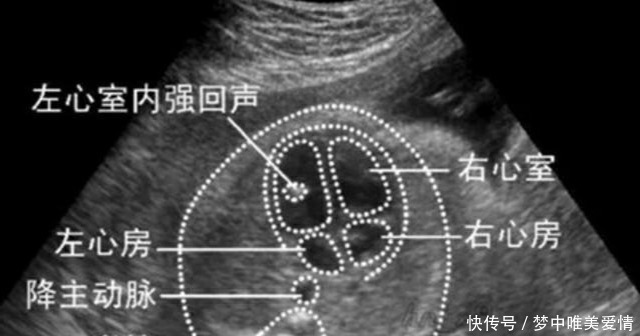

做四维彩超说胎儿正常,出生后检查出有严重的心脏病大动脉完全转位。医院有责任吗?四维彩超所针对的检查有胎儿颜面部是否有明显的畸形,四肢是否存在缺失或者畸形发育,以及内脏及各器官发育。而对于畸形筛查必须要检查出来的畸形有:无脑儿、脊柱裂、四肢、心室等。也就是说对于畸形筛查,四维彩超会存在一定的误差,而误差中也包括孕妇和胎儿的原因,如:孕妇太胖,腹部脂肪厚、胎儿在宫内的位置不利于检查。当然了,检查时医务人员技术水平的高低也是一种因素。

就畸形筛查来说,在检查前都会让孕妇签免责书的,也就是说,畸形筛查检查胎儿正常,但是胎儿出生后存在一定的畸形,那么只要畸形范围在畸形筛查误差范围内,也就是误差范围内,那么医院是不用承担相关责任的,或者是即使进行相应的补偿,也是出于人道主义关怀。而对于超声误差范围有:四肢末端,如:手指脚趾,耳朵、眼球、以及其他的脏器。这是因为畸形筛查的超声检查中,可以检查出最低60%的胎儿畸形发育,而剩下的漏诊率,最高在40%。而胎儿心脏,虽然说是非常重要的器官,但是也没有明确的表明畸形筛查中需要100%的检查出关于心脏的畸形。并且,因为胎儿心脏是持续不断的发育,变化的,即使畸形筛查时正常,在之后孕周的发育时,也可能会逐渐的出现异常发育,这也就导致即使畸形筛查正常,但是因为后期胎儿发育出现异常,所以胎儿出生时有畸形。

□因为畸形筛查存在一定的误差,所以就心脏检查而言,孕妇可以在孕周大些的时候再做胎儿心脏彩超:虽然说畸形筛查做四维彩超时会检查胎儿心脏,但是那也只是属于系统性的检查,并不能做到很精密的针对于胎儿心脏发育的检查。所以,为了胎儿的健康考虑,孕妇在畸形筛查后都应当再做一个胎儿心脏彩超。这并不是说非得畸形筛查胎儿心脏有异常指标的才能做,正常的也可以做。胎儿心脏彩超是针对于胎儿心脏的检查,可以说是针对胎儿心脏发育比较精密的检查,一般来说,如果有异常,那么是能够看出来的。虽然说心脏彩超就畸形筛查需要另付费用,但是为了胎儿的健康,我觉得还是有必要做的。而胎儿心脏有严重的心脏病,大动脉完全转位这种畸形发育我们不能盲目的判断是医院的责任,家长还是请专业人士来判断吧。